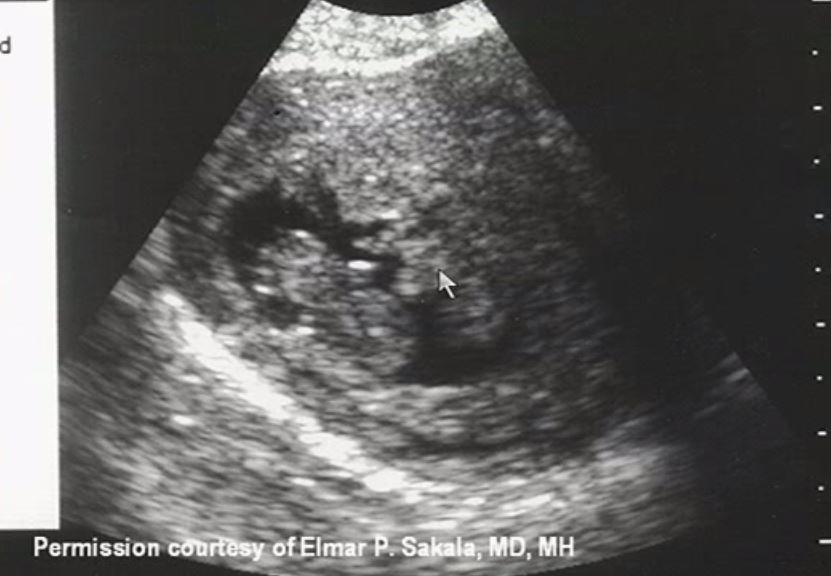

VEamos unos ecos

aborto completo